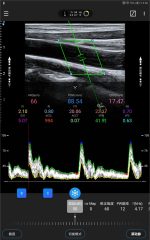

Prueba de prevención cardiovascular

Autorreconocimiento y automedición de IMT

Galería de demostración

|